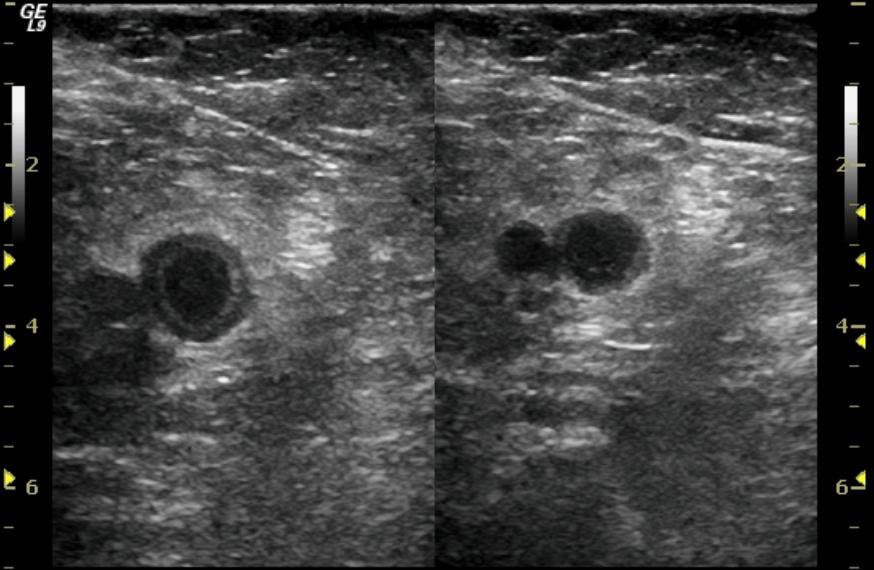

Is this a new clot?

Knowing the difference between an acute clot and residual clot is not always straightforward. Furthermore, patients who have had a thrombotic event often also have residual symptoms such as chronic leg pain or discoloration. This matter has been addressed in the recent issue of the Journal of Thrombosis and Haemostasis. The authors summarized available literature to offer practical easy to follow guidelines for clinicians suspecting thrombosis recurrence. The authors suggest appropriate use for clinical prediction tools, d-dimer testing and imaging. The original article can be found here and our summary can be found here.